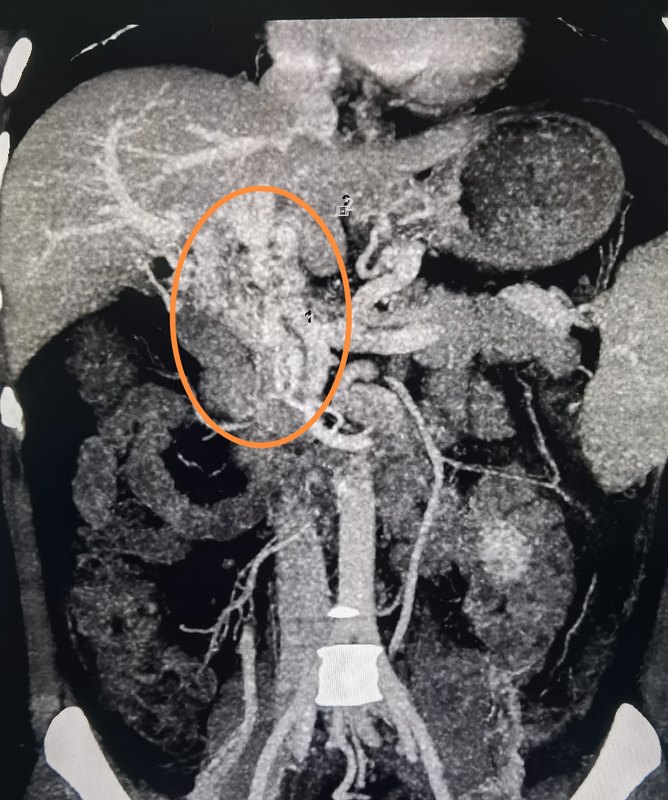

門(mén)靜脈海綿狀變性(cavernous transformation of portal vein,CTPV)這幾天收治了一個(gè)膽囊結(jié)石的患者,入院超聲檢查提示門(mén)靜脈主干血栓,門(mén)靜脈海綿樣變性。包括小伙伴們?cè)趦?nèi),一些住院醫(yī)師也問(wèn)我“楊老師,這個(gè)海綿樣變性是什么意思???”。今天我就給大家講一講這個(gè)“海綿樣變性”。“海綿樣變性”和海綿體完全不是一回事,老司機(jī)們別亂想,哈哈!首先和大家科普一下,什么是門(mén)靜脈。門(mén)靜脈是腸系膜上靜脈,腸系膜下靜脈及脾靜脈匯合后形成的一個(gè)進(jìn)入肝臟的靜脈血管。它將來(lái)自胃、小腸、大腸及脾的血液,及來(lái)自胃腸道的營(yíng)養(yǎng)物質(zhì)匯集在一起,輸送給肝臟。而這些物質(zhì)由肝臟解毒,并合成各種人體需要的物質(zhì)后再經(jīng)肝靜脈回輸給腔靜脈,之后再進(jìn)入心臟,發(fā)送給身體的各個(gè)部位。下面我們回到主題,海綿樣變性。在長(zhǎng)期存在的門(mén)靜脈血栓形成的背景下,血栓再通、門(mén)靜脈側(cè)支靜脈逐漸形成,側(cè)支靜脈管徑逐漸增大,在肝門(mén)內(nèi)形成了大量側(cè)支靜脈。這種現(xiàn)象被稱為門(mén)靜脈的海綿狀變性。在超聲影像上,門(mén)脈周圍有許多蛇形的血管,而門(mén)靜脈主干卻不顯示。當(dāng)然這些側(cè)支血管的血流方向還是向肝臟去的。在慢性門(mén)靜脈血栓形成和海綿狀轉(zhuǎn)變中,肝臟的形態(tài)可能會(huì)發(fā)生扭曲,I段和Ⅳ段增大,其他肝臟周圍可能出現(xiàn)萎縮。門(mén)靜脈血栓可能是由高凝狀態(tài)、炎癥性疾病、膿毒癥、骨髓增生性疾病、腫瘤以及常見(jiàn)的門(mén)脈高壓引起的。超聲提示門(mén)靜脈管腔內(nèi)的固體物質(zhì),可能是無(wú)回聲、低回聲、等回聲或高回聲。門(mén)靜脈直徑可正常或增大。多普勒模式下可以看到血管內(nèi)無(wú)彩色血流或顏色不完整。“楊大夫怎么開(kāi)始講超聲了呢?”哈哈!對(duì)的,楊大夫作為一個(gè)外科醫(yī)生,超聲技術(shù)還是很高的哦。這可是在斯坦福大學(xué)進(jìn)修期間專門(mén)學(xué)習(xí)的技術(shù),作為一名肝膽胰外科醫(yī)生,熟練應(yīng)用術(shù)中超聲,會(huì)使手術(shù)更加得心應(yīng)手。怎么區(qū)分單純的血栓還是腫瘤的瘤栓呢?單純的血栓是個(gè)大充盈缺損,多普勒模式下無(wú)血流。而腫瘤血栓可以看到血栓內(nèi)動(dòng)脈波形。這是一個(gè)特定的發(fā)現(xiàn),但不是很敏感。US造影可以提高門(mén)脈血栓的診斷率。但是作為外科醫(yī)生,我們的超聲技術(shù)側(cè)重于術(shù)中超聲“IOUS”,所以超聲造影這個(gè)事,楊大夫是不做的。我還是傾向于術(shù)前完善增強(qiáng)CT或者增強(qiáng)磁共振來(lái)明確診斷。這是一張CT三維重建的腸系膜上靜脈-門(mén)靜脈系統(tǒng)的海綿樣變性的圖片,是不是像海綿。這個(gè)圖就是門(mén)靜脈造影顯示出來(lái)的門(mén)靜脈海綿樣變性。門(mén)靜脈海綿樣變性會(huì)怎么樣呢?其實(shí)海綿樣變性就是因?yàn)楦鞣N各樣的原因所致的門(mén)靜脈梗阻,所致門(mén)脈高壓,大量側(cè)支循環(huán)形成引起的,手術(shù)時(shí)大出血地風(fēng)險(xiǎn)極大。所以對(duì)待這樣的患者,要像對(duì)待肝硬化引起的門(mén)脈高壓一樣,如果不了解這一點(diǎn),而貿(mào)然的進(jìn)行手術(shù),尤其是肝膽系統(tǒng)的手術(shù),可能會(huì)帶來(lái)災(zāi)難性的后果。